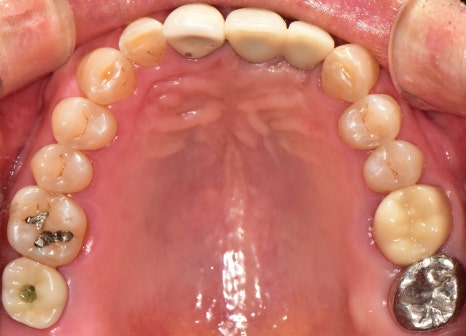

내원 당시 구강 속을 살펴보면

잇몸이 붓고 내려가 있으며

떨어져버린 어금니가 있고,

여기저기 많이 닳아있으며

아예 상아질이 드러난 것을

문정동치과 에서 체크할 수 있었는데요.

문정동치과 에서

잇몸치료를 병행하며,

임플란트 뼈이식으로

앞니, 어금니 보철 식립을

해드린 결과입니다.

치열이 좀 비뚤어져 있는 것은

아쉽긴 합니다만,

처음 상태와 비교해봤을때,

많이 개선된 것을 확인할 수 있었습니다.